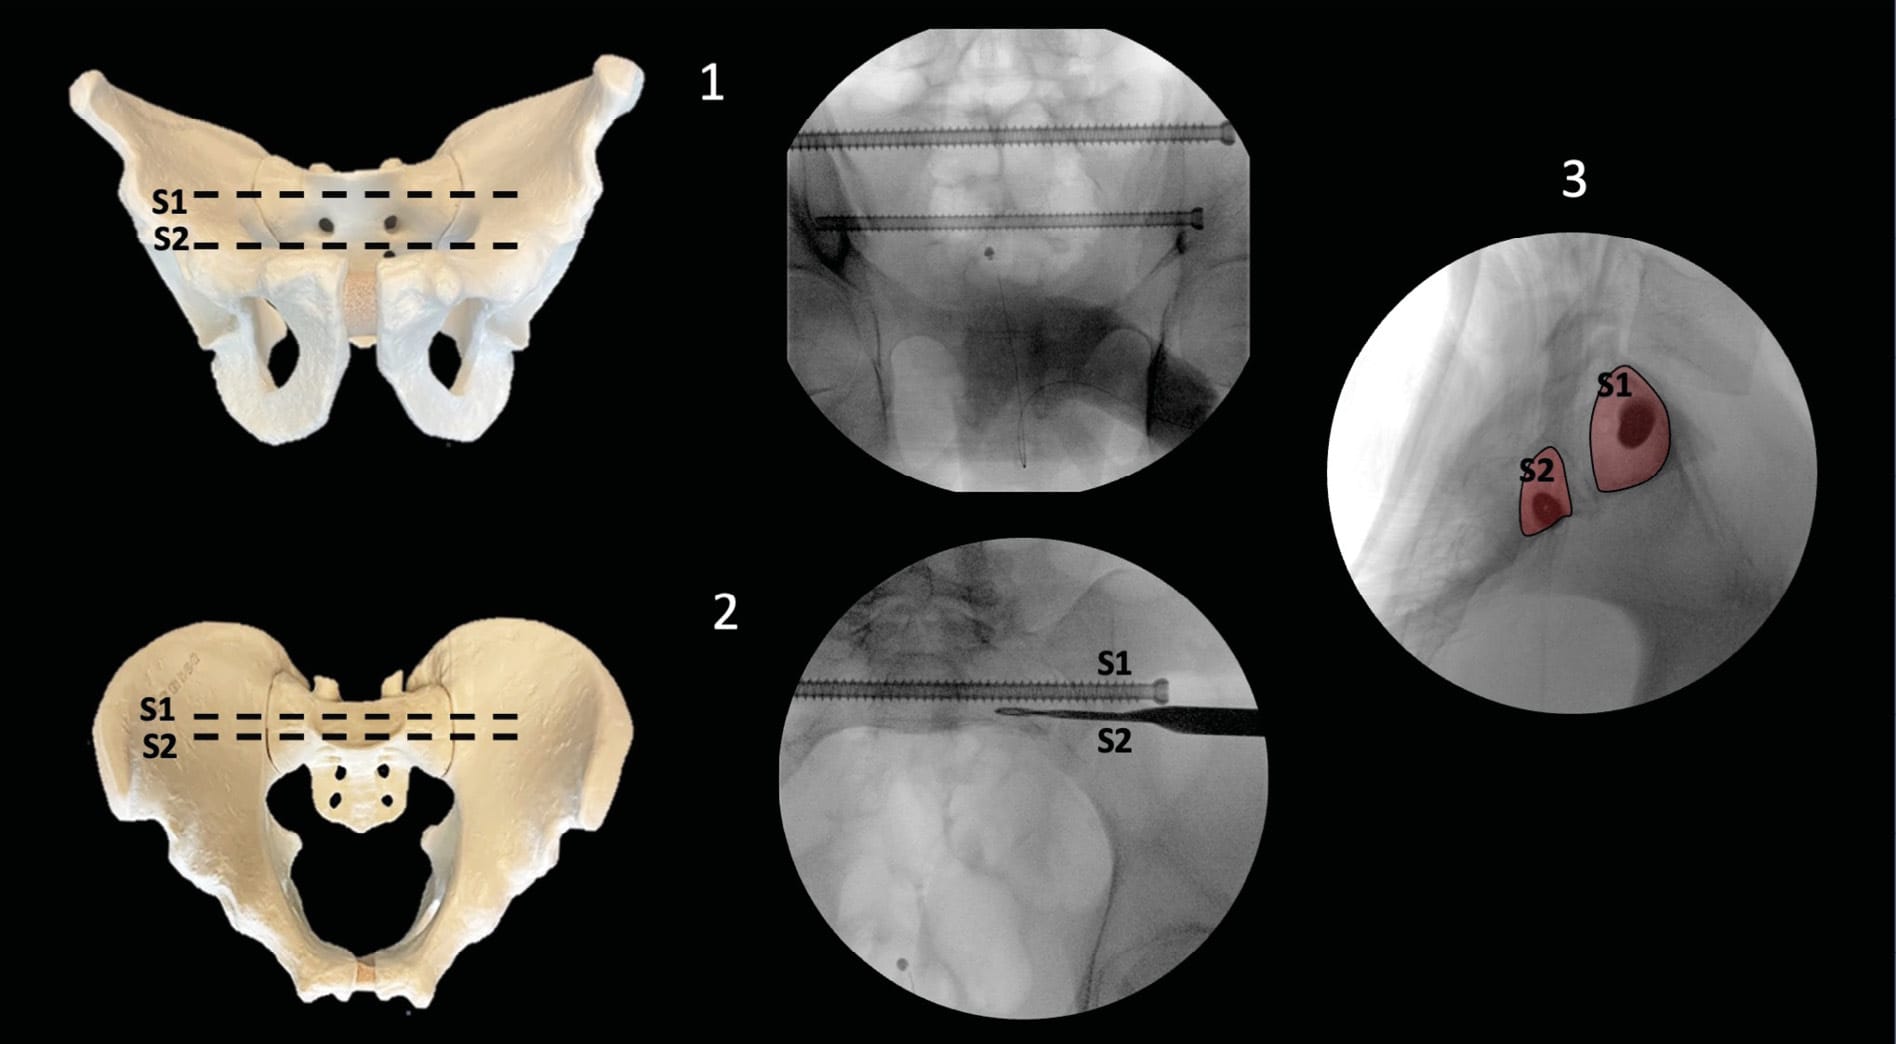

The coxal bone is structured as a flat bone, composed of trabecular tissue enclosed between two layers of cortical tissue. Its role in standing and sitting positions requires an architecture adapted to these two functions, as found in all other skeletal structures, with a specific arrangement of bone trabeculae in response to the pressures experienced and transmitted by the bone. According to the work of anatomists Latarjet and Gallois, the architecture of the pelvis is organized into two distinct systems. The first extends from the auricular facet to the acetabular cavity and is adapted to standing or walking: it consists of sacro-acetabular trabeculae. The second, starting from the same surface and ending at the ischium, is adapted to the sitting position: it is formed by sacro-ischiatic trabeculae. These bone trabeculae are the basis for Letournel's theory of acetabular columns and the corridors described for percutaneous surgery (Figure 1).

An anteroposterior view quickly reveals any craniocaudal displacement of the pelvic ring or femoral head protrusion into the acetabulum. The acetabulum is evaluated using obturator and iliac oblique views, obtained by 45-degree axial rotation around the patient, allowing analysis of the landmarks described by Letournel. Inlet and Outlet views, described by Pennal et al. [13] Pennal GF, Tile M, Waddell JP, Garside H. Pelvic disruption: assessment and classification. Clin Orthop 1980:12–21., enable analysis of the pelvic ring. The Inlet view is a superimposition of the anterior landmarks of the S1 and S2 vertebral bodies. Visibility of the sacral canal and S1 vertebral body serves as a good quality criterion. It allows identification of anteroposterior hemipelvic translation.

The Outlet view, defined as the superimposition of the pubic symphysis apex with the S2 vertebral body, allows identification of vertical translation of a hemipelvis. This view is crucial for identifying signs of lumbosacral junction dysplasia. The numerical value of these inclinations may vary depending on pelvic version, and radiographic criteria should be used as quality indicators rather than specific values.

Finally, the true lateral view, as described by Routt, where perfect superimposition of both greater sciatic notches constitutes the quality criterion. It enables identification of S1 and S2 vertebral bodies, as well as the two iliac cortical density lines, located at the anterior portion of the sacroiliac joint and extending forward through the pelvic brim. These landmarks prove useful during guide wire advancement. (Figure 3)

These techniques can be performed in either supine or prone position; however, to minimize anesthetic complications in trauma patients, the supine position is preferred. The starting point for screw placement can be determined using a lateral view. The main fluoroscopic views used are the Inlet and Outlet views. The Inlet view shows the anteroposterior boundaries, while the Outlet view guides the caudocranial trajectory. A lateral view can be used for the entry point, but primarily to secure the trajectory in relation to the lumbosacral trunk. Finally, an Inlet + Obturator view will allow monitoring of the external table of the tuberosity and thus the length and application of the screws. (Figure 3)